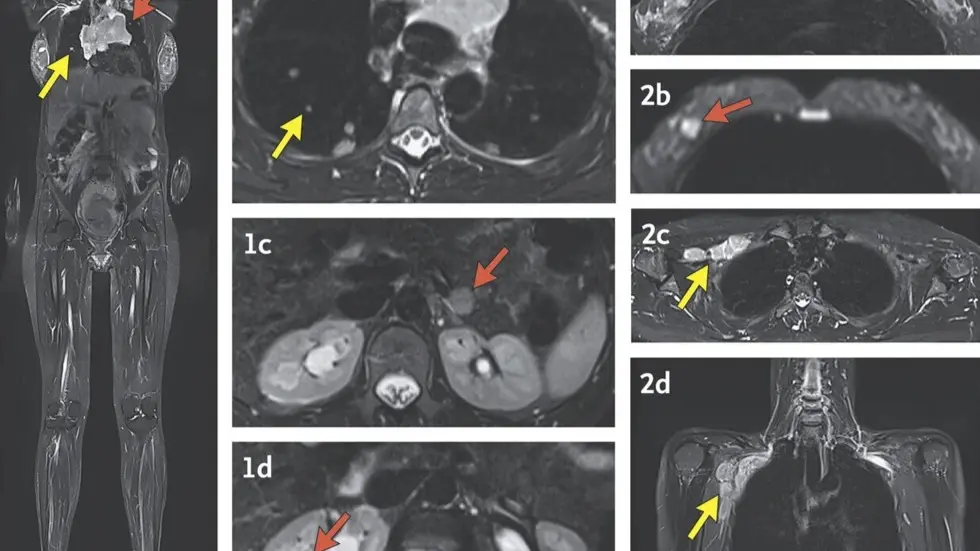

The study looked at what should be done next, and the researchers concluded that it's best to do a whole-body MRI to look for cancer. A physical exam or taking a family history is not enough, Bianchi said.

About five years ago, commercial labs that do these tests and doctors started telling women with unusual results about the study. The National Institutes of Health paid for study volunteers to travel to its research hospital in Bethesda, Maryland, where the participants had their family and medical histories reviewed, a complete physical examination, whole-body MRI scans and other tests performed.